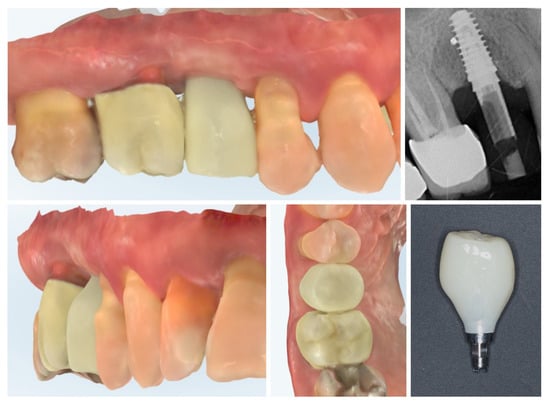

Digital scans obtained at delivery of the definitive prosthetic reconstructions show stable integration of both the implant-supported crown in region 15 and the full-contour zirconia crown on tooth 16 (Figure 17). The emergence profile of the implant-supported crown completely copies the profile of the temporary crown in order to not induce changes in the crestal bone. The peri-implant soft tissues demonstrate healthy contours and harmonious adaptation to the restoration’s emergence profile. The occlusal and proximal relationships are well-preserved, ensuring functional loading and esthetic integration with adjacent teeth. No soft tissue recession or volumetric loss is evident, confirming the stability of the roll flap augmentation and the favourable outcome of the prosthetic phase.

Figure 17.

Clinical view of the final implant-supported and tooth-supported crowns (8 months post-op).

Clinical view at 6 months following delivery of the definitive prosthetic restorations demonstrates stable peri-implant and periodontal soft tissues (Figure 18). The mucosal margin is healthy, with adequate buccal thickness and harmonious integration of the implant-supported crown in region 15 and the adjacent tooth-supported crown in region 16. No signs of inflammation, mucosal recession, or soft tissue collapse are evident, confirming long-term stability of the roll flap augmentation and successful functional and esthetic rehabilitation. The X-ray control shows stable crestal bone levels.

Figure 18.

Clinical appearance and X-ray control 6 months after definitive prosthetic treatment (14 months post-op).